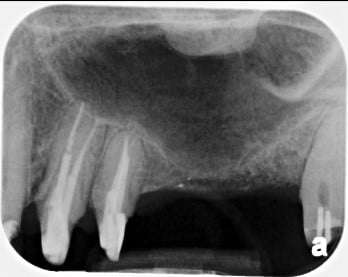

An external sinus lift, where there is very little or no bone to work with, is performed before the actual implant placement and usually covers the floor of the sinus on one side below its protective membrane.

An example of an external sinus lift can be seen below:

Stage 1: No Bone Available to Receive any Implant

Stage 2: Bone Graft Placed in an External Sinus Lift

Stage 3: Implants Placed in the Matured Bone Graft